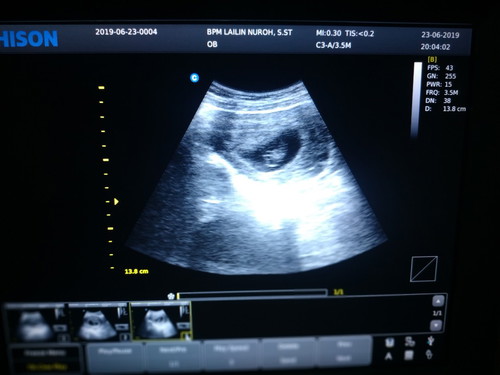

Bunda AQ pernah ngalami keguguran dan d kuret Maret 2018,dan Mei 2019 sudah hamil lagi. Pas waktu periksa ke puskesmas bidanya bilang kehamilan resiko tinggi karena jarak nya masih dekat dengan keguguran...tp AQ USG ke dokter Alhamdulillah kandungan sehat....

Sama kaya saya Bun .. saya kuret bulan mei 2019 trs Juli positif hamil.. awalnya Juga khawatir karena baru haid pertama setelah kuret trs bulan berikutnya sudah positif.. pas tau hamil saya langsung periksa dan langsung usg transvaginal di usia kandungan 4w,Alhamdulillah sudah terlihat kantung kehamilan..bulan berikutnya usia 8w saya USG lagi Alhamdulillah bakal janin sudah kelihatan dan sudah ada djj nya.. sekarang kahamilan saya sudah 36w..

Baca lagiSaya keguguran yg ke 2 dibulan oktober akhir Selesai nifas desember awal saya tunggu2 haid tak kunjung dtang di januari 2020 saya testpack hasilnya + saya kepuskesmas, mereka bilang kayak gtu, pas usg alhamdulillah sehat, doktrnya blg jga gpp yg pnting jgn jalan jauh n banyak istrahat di 5 bulan awal kehamilan😊